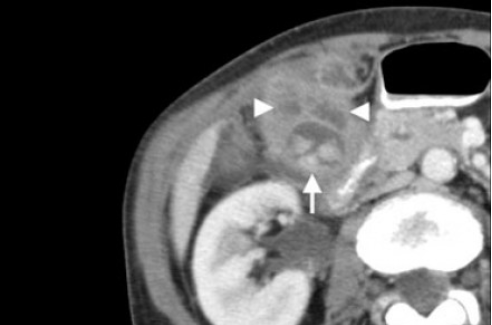

(Левый) У женщины 37 лет с острыми болями в правом верхнем квадранте живота на сагиттальном УЗ срезе желчного пузыря визуализируются отбрасывающие тень конкременты и сладж, а также опухолевидное дольчатое локальное утолщение стенки, прорастающее трансмурально.

(Правый) При КТ с контрастным усилением в режиме мульти планарной реконструкции в той же сагиттальной плоскости определяется полипоидное объемное образование стенки желчного пузыря, накапливающее контраст.

(Слева) На аксиальной КТ с контрастным усилением определяется распространенное круговое утолщение стенки желчного пузыря, которое проспективно было расценено как проявление ксантогранулематозного холецистита. Тем не менее, во время оперативного вмешательства обнаружился рак желчного пузыря.

(Справа) На сонограмме визуализируется объемное образование в ямке желчного пузыря и конкрементдающий акустическую тень. Образование не отделено от прилежащих отделов печени. На КТ (томограммы не продемонстрированы) была обнаружена локальная инвазия рака желчного пузыря в центральные отделы печени.